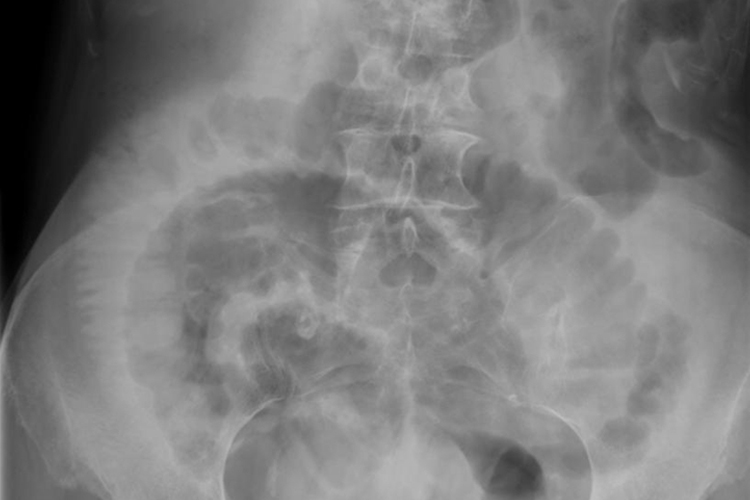

肠梗阻的X线表现为肠腔内气体影,立位或卧位摄片可见液平面及胀气肠襻。同时患者可伴有腹痛、呕吐、腹胀等症状。

一般在肠梗阻发生4-6小时后腹部X线摄片可显示出肠腔内气体影,立位或卧位摄片可见液平面及胀气肠襻。有时空肠黏膜环状皱襞可显示“鱼肋骨刺”状,结肠梗阻时胀气位于腹部周边,显示结肠袋形。如液平面呈阶梯状,则提示小肠梗阻。如显示“同心圆”X线征象时,应考虑肠套叠。